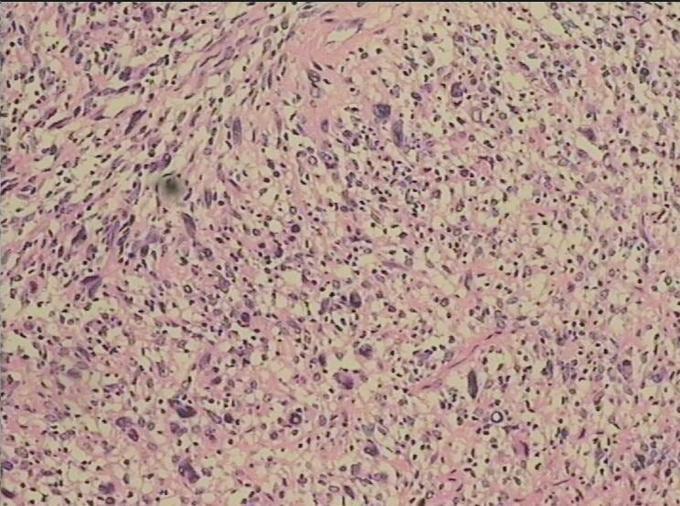

诊断:(左小腿肌肉肿瘤)肉瘤 治疗:在全麻下行 左小腿肿瘤切除术,术后给予对症治疗及相应的理疗及功能锻炼,患者症状明显缓解,切口愈合好。术后病理示:(左小腿肌肉肿瘤)肉瘤,恶性外周神经鞘瘤,低度恶性。

随访:术后随访中。 讨论:肿瘤位于深部组织,无明显自觉症状或稍有不适感,生长缓慢。肿瘤的大小与病程长短有关,直径从数厘米到十几厘米。肿瘤周界不清,表面光滑,无压痛,质坚韧如橡皮。与侵犯肌肉的纵向较固定,而横向稍能移动,与皮肤无粘连。巨大肿瘤可影响活动和压迫神经。